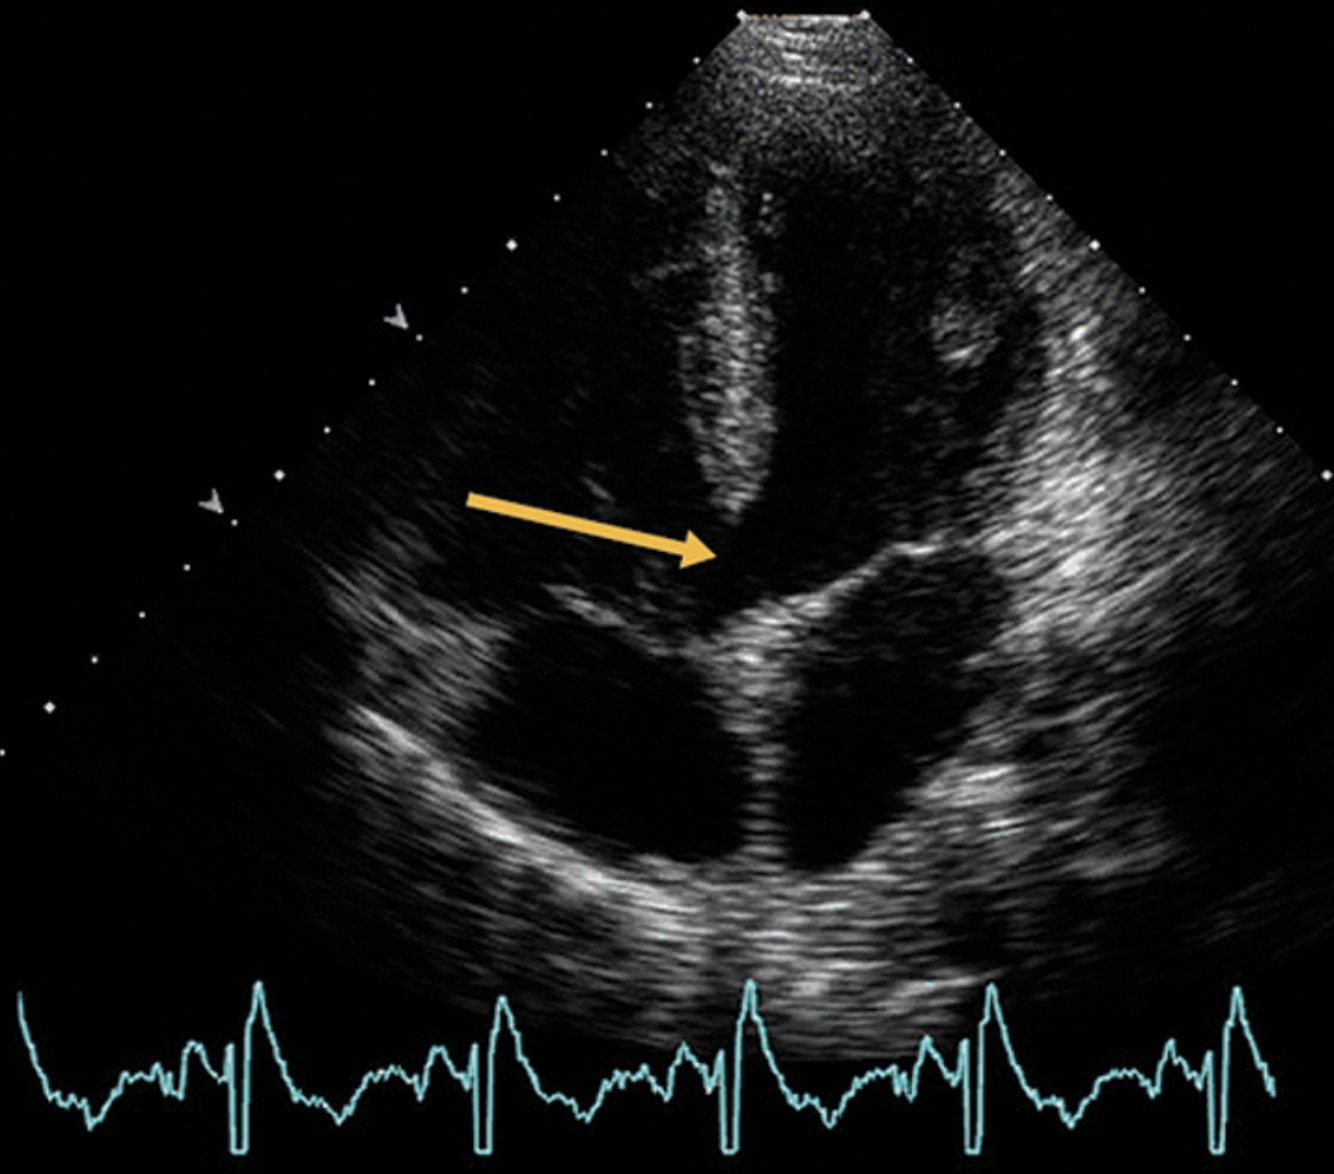

Which echocardiographic scan plane is most optimal to define a secundum ASD?